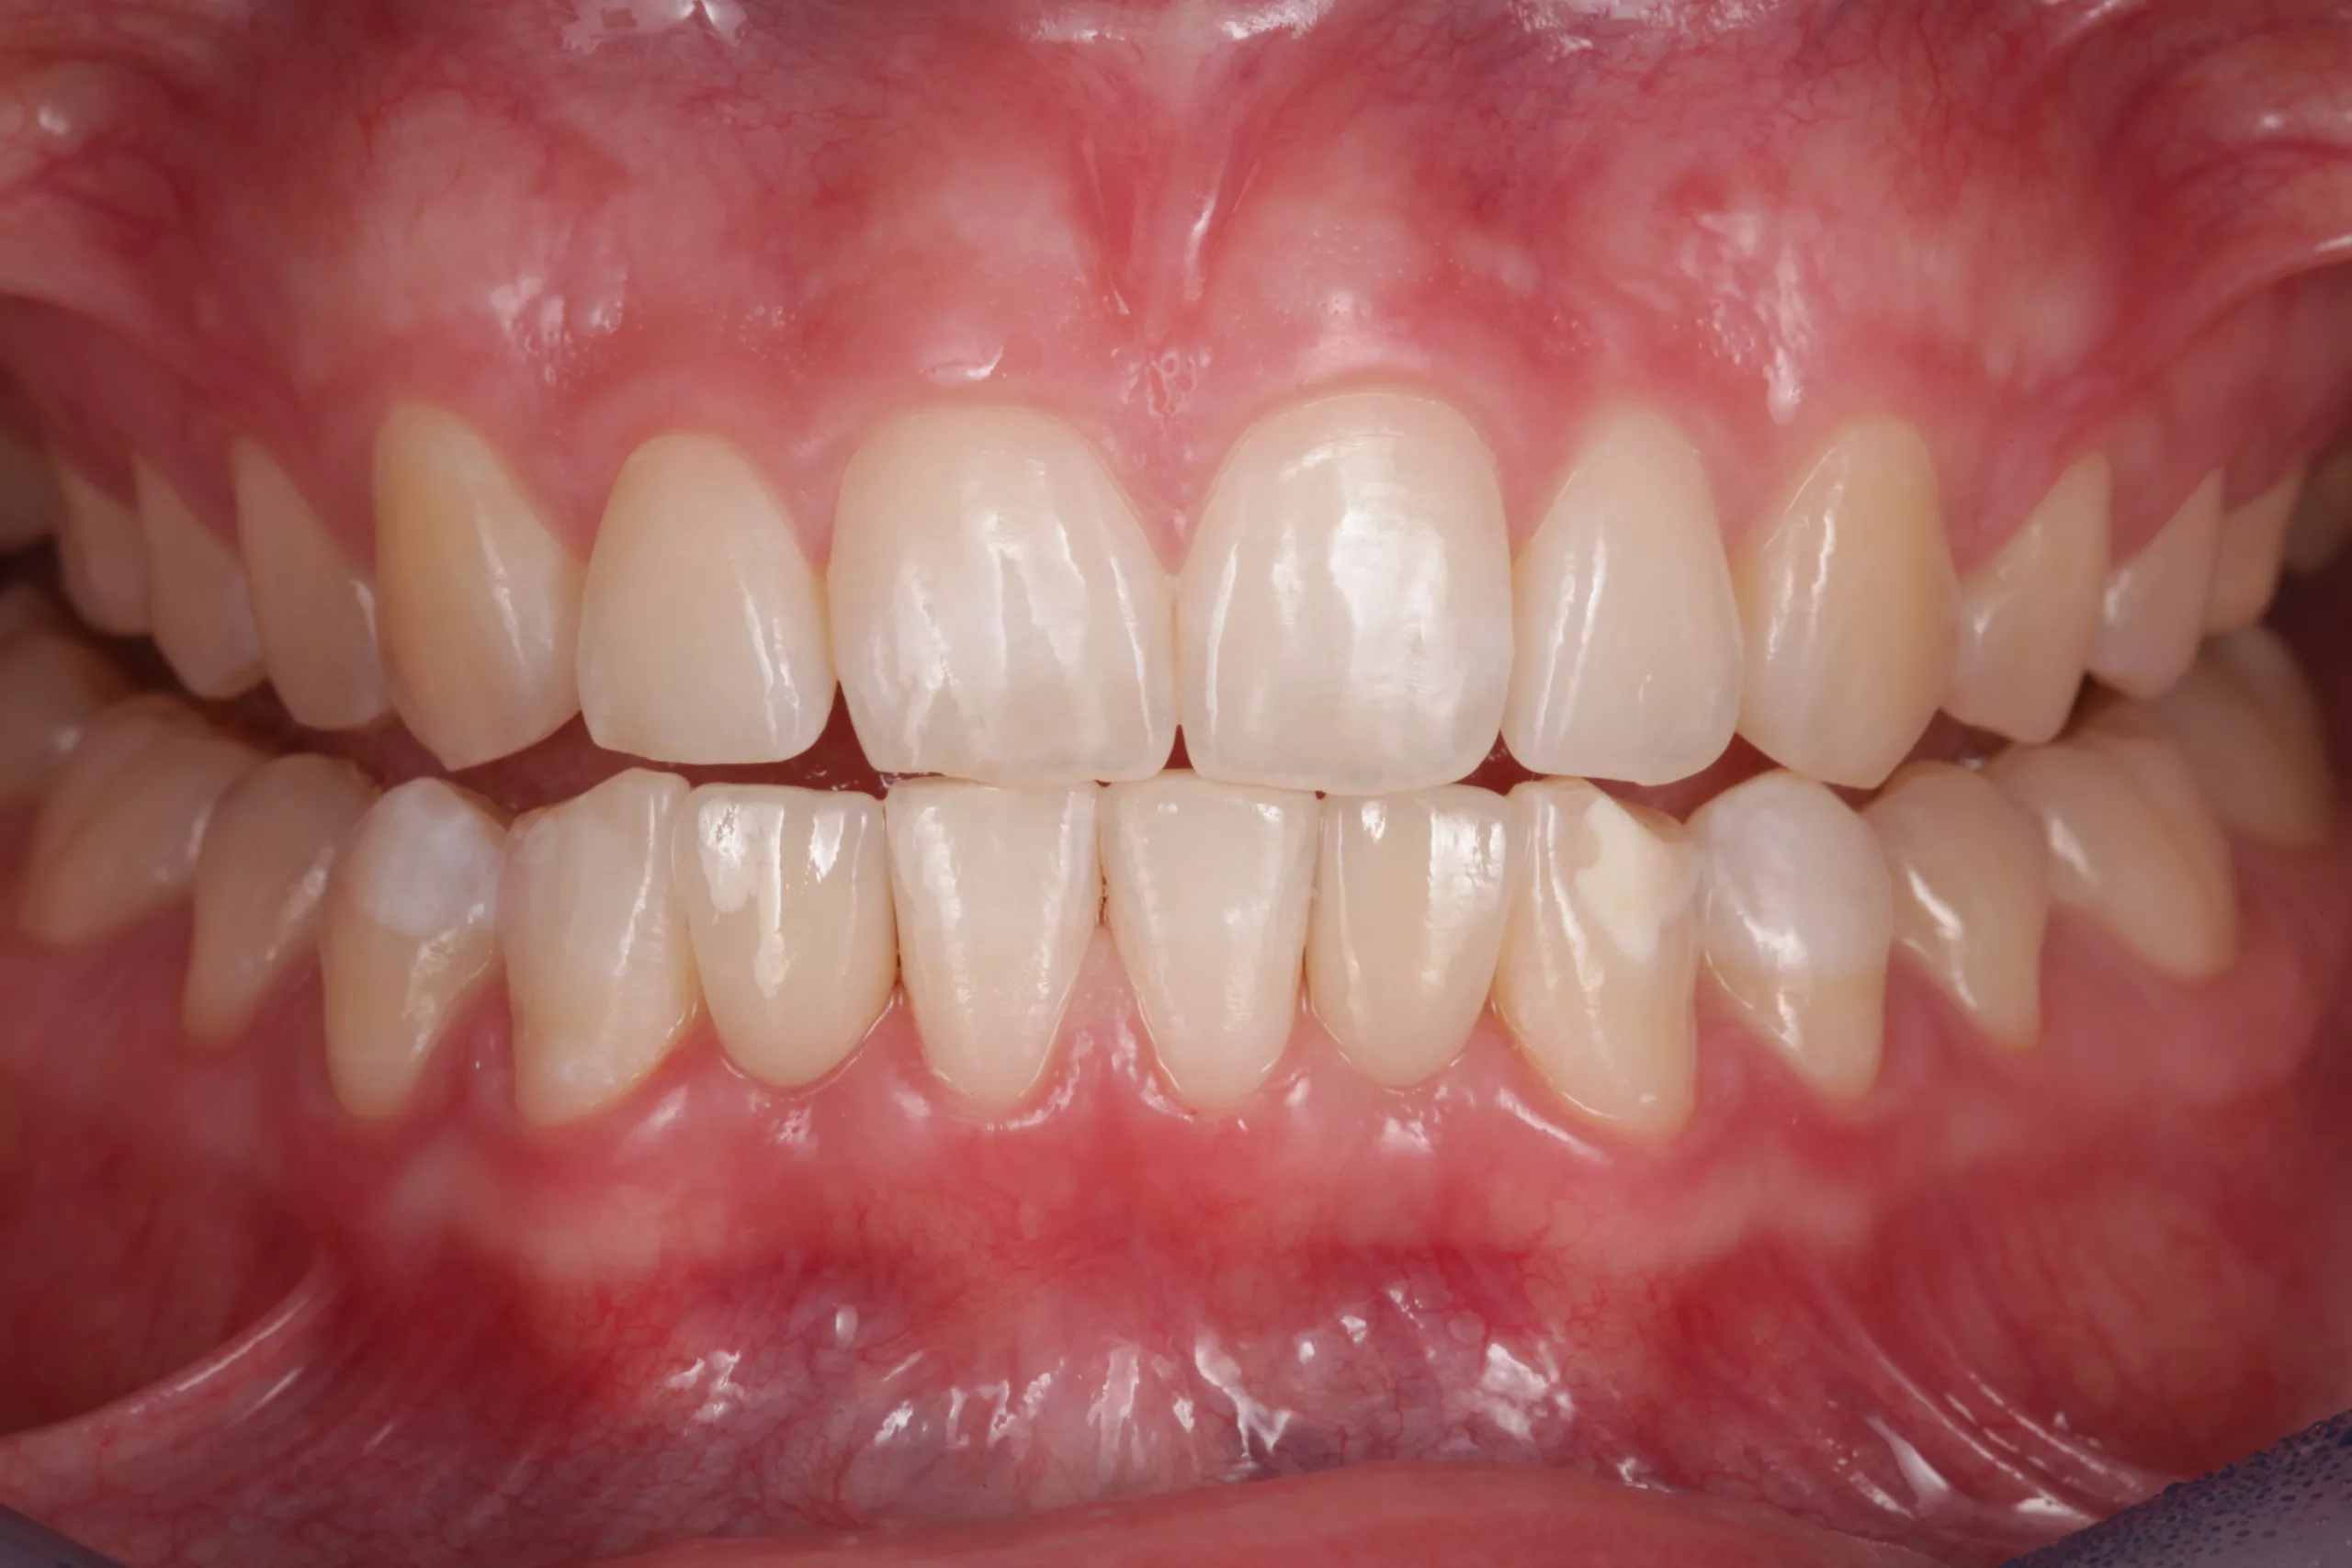

Eine 17-jährige Patientin stellte sich nach kieferorthopädischer Vorbehandlung alio loco und bereits erfolgter Lückenöffnung regio 32, 42 bei Nichtanlage 31, 41 in der Klinik für Zahnärztliche Prothetik und Biomaterialien, Zentrum für Implantologie des Universitätsklinikums Aachen mit dem Wunsch nach einer Lückenversorgung vor (Abb. 2-4). Die Lücken wurden mithilfe eines herausnehmbaren Zahnersatzes (Interimsprothese) offen gehalten. Nach aktiv- kieferorthopädischer Therapie sollten mindestens 6 bis 8 Wochen als Retentionszeit vor der definitiven, festsitzenden prothetischen Versorgung kalkuliert werden [7].

Okklusion und Artikulation können nun überprüft und ggf. angepasst werden. Abschließend folgt die Instruktion des Patienten zur effizienten Reinigung im Bereich der Adhäsivbrücke. Eine Situationsabformung mit anschließendem Situationsmodell und die fotografische Dokumentation des klinischen Ergebnisses helfen bei den Nachsorgesitzungen zur Kontrolle etwaiger Veränderungen der Pfeilerzahnstellung (Abb. 13- 15).